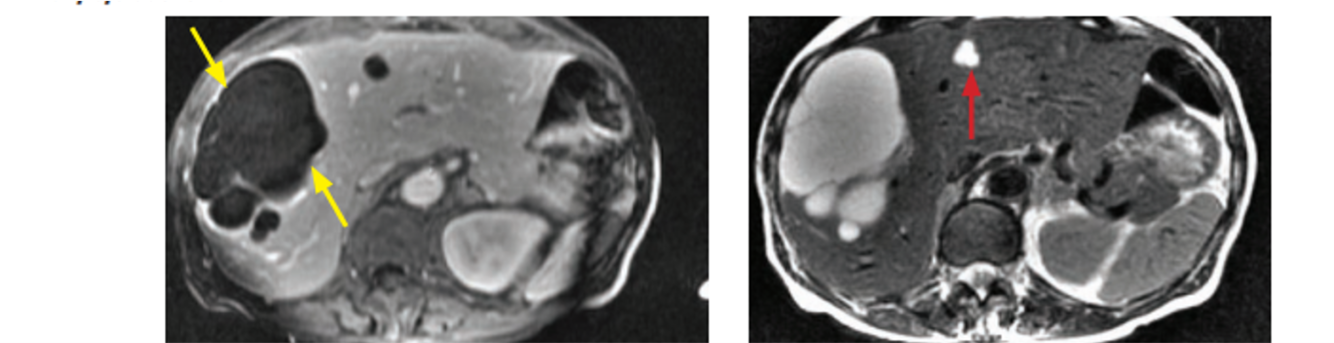

Caroli disease (todani type V) plus ADPKD

Caroli’s is associated with medullary sponge kidney and ADPKD and ARPKD

caroli disease (todani type V)